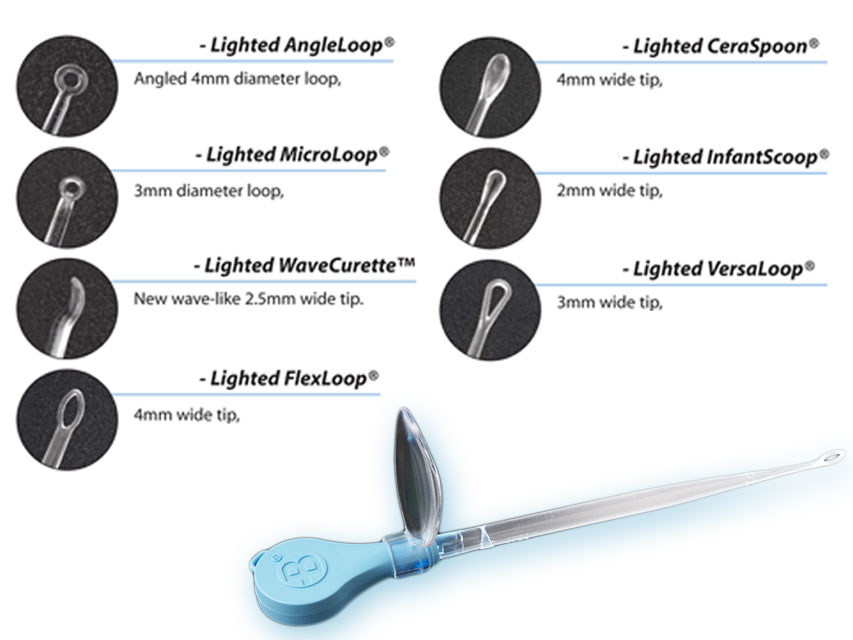

All’interno sono disponibili curettes auricolari, speculum auricolari e speculum nasali, strumenti essenziali utilizzati per l’esame e il trattamento delle vie uditive e nasali in contesti sanitari e professionali.

All’interno sono disponibili curettes auricolari, speculum auricolari e speculum nasali, strumenti essenziali utilizzati per l’esame e il trattamento delle vie uditive e nasali in contesti sanitari e professionali.